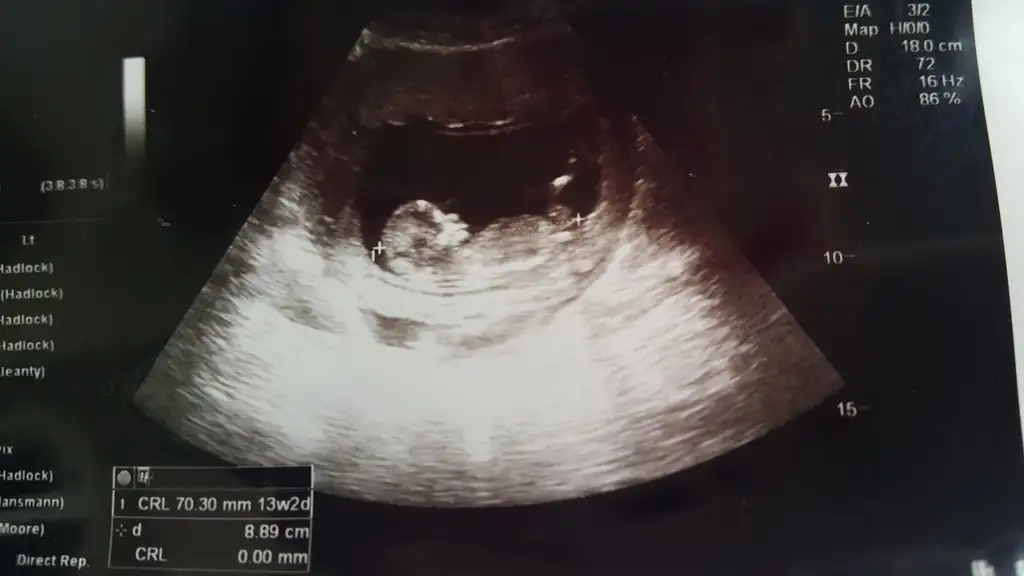

Cok şükür Rabbime hiç bir sıkıntı yokmuş. 13+2 ymiş adetten 1 hafta ilerideymiş..